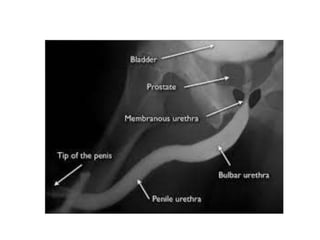

Chụp niệu đạo bàng quang

• Mục đích:

• Kỹ thuật:

Bơm thuốc cản quang vào niệu đạo qua ống thông Foley.

Lượng thuốc tùy thuộc vào độ dài và độ lớn của niệu đạo.

Chụp 1 phim thẳng- chếch.

ngược dòng